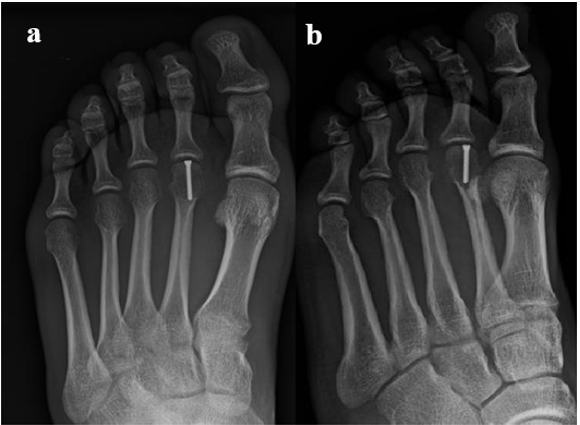

A 19-year-old male presented at our emergency department with a history of left foot trauma when landing from a jump, with the toes in hyperextension. He reported immediate onset of acute pain and inability to perform weight bearing as well as dorsal swelling over the second metatarsophalangeal joint. He denied any significant past medical history or any current medications. Physical examination revealed swelling, bruising and pain over the left second metatarsal head. He presented painful mobilization of the second metatarsophalangeal joint as well as crepitation on palpation and had no neurovascular impairment. Plain radiographs, with oblique and anteroposterior views, of the left foot revealed an osteochondral fracture of the second metatarsal head (Figure 1). Due to the nature of the lesion and fracture pattern, a CT scan was preformed, showing a slipped retroverted osteochondral fragment (Figure 2).

Figure 2: CT scan images in the axial, coronal and sagittal planes showing the intraarticular slipped retroverted osteochondral fragment.